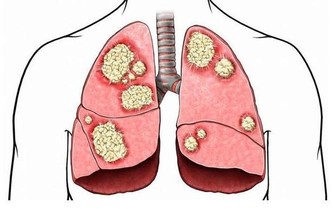

- 心血管疾病:高熱量、高脂肪飲食容易導致血管堵塞,增加心臟病和中風風險。